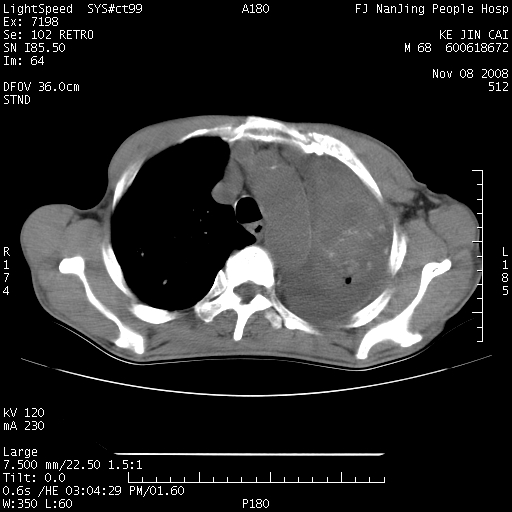

是个很有看头的病例,咋人气那么不旺?没多少人兴趣呢?这个病例几大怪:1   恶性肿瘤侵犯心肌左房怪,心肌一般不会被恶性肿瘤侵犯吧?2   左下肺均匀实变怪,内无含气,有别一般不张实变,含气肺泡完全为液体取代,而非一般不张实变的肺萎陷,冷不丁还以为是肿大的脾脏3   肿瘤本身怪,像tb肺不张4   这么有看头的病例没人气怪。呵呵。

追查病史,咳嗽,患者无发热,血象不高。据说2年前胸片检查怀疑肺ca曾行纤支镜检查,病理未见到癌细胞。无确切资料。

左肺恶性肿瘤侵犯肺动脉,左心房内瘤栓,胸膜转移。

左肺恶性肿瘤侵犯肺动脉,左心房内瘤栓,胸膜转移,少见,学习了。